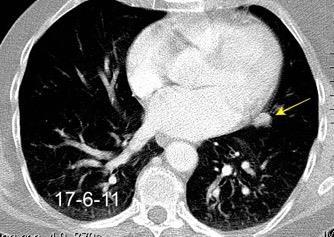

Masa axilar izquierda y derrame pleural derecho. Implantes pleurales, paraespinales . Ganglios en mamaria interna. Linfoma B difuso

2011. Acude por masa axilar

Linfoma NH de cél. B. Invasión Transtorácica.

Afectación axilar

Nódulo en língula.